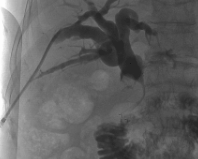

最终,于主任与血管外科代伟、浦玺斌两位医生通力协作,运用血管外科器械再次操作。这一次,导丝顺利地穿透了梗阻的部位,就像一座山没有一点缝隙,在山体打通了一条隧道。基于此,胆道扩张金属支架被成功置入,王奶奶梗阻的胆道终于变畅通了。引流袋管子怎么不流告别引流袋,老人的心愿终于实现!_https://www.jmylbn.com_新闻资讯_第4张引流袋管子怎么不流告别引流袋,老人的心愿终于实现!_https://www.jmylbn.com_新闻资讯_第5张引流袋管子怎么不流告别引流袋,老人的心愿终于实现!_https://www.jmylbn.com_新闻资讯_第5张

引流袋管子怎么不流告别引流袋,老人的心愿终于实现!_https://www.jmylbn.com_新闻资讯_第7张

▲置入支架后,梗阻的胆道被打通